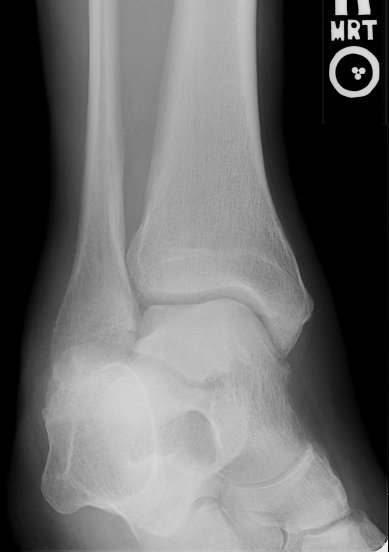

Return to Weber A Fracture